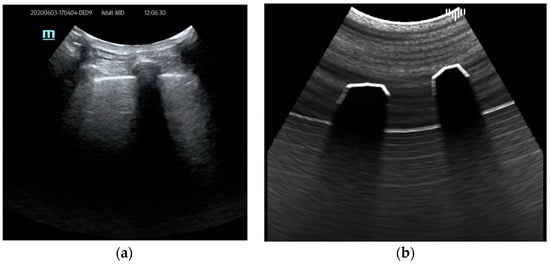

In addition to the mentioned artifacts that are highly important during lung ultrasound examinations, it was crucial for educational purposes to simulate the presence of consolidation. Consolidations are regions of lung tissues filled with liquid instead of air. It ensues from the accumulation of inflammatory cellular exudate within the alveoli and contiguous ducts. The simulation of the image of consolidation was achieved using a predefined mesh object created in 3D software (3D Studio Max, Autodesk) and positioned in a virtual patient interior. Material attributes are added to the consolidation object to increase attenuation and induce more reflectance and then rendered in the final image (Figure 6).

Figure 6. Consolidation example: (a) real examination; (b) the LUS simulation.